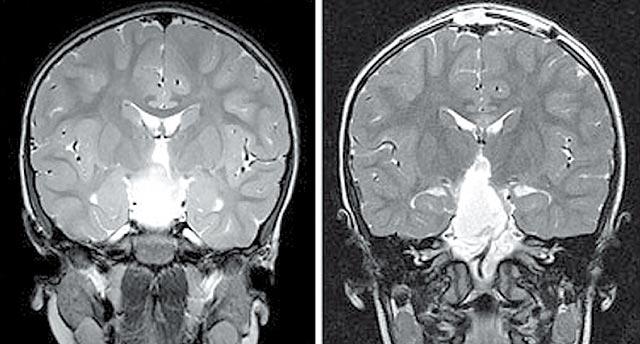

腫瘤是良性,但位於腦部深處,周圍有很多神經線,五年前仍是不治之症。現在,因有磁力共振造影技術,能鎖定腫瘤位置,為醫生導航,將腫瘤切除。

「腫瘤很大,很難搞。」醫生謝德(StevenShedd)去年為韋伯斯特進行手術時,發現腫瘤闊度達3.23厘米,像乒乓波一樣。手術長達九小時,十分危險。